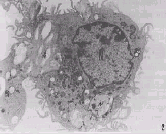

(一)煤斑

煤塵肺CT煤斑是煤工塵肺最常見的原發性特徵性病變。雖非特異,但應列為診斷的基礎指標。肉眼觀察呈灶狀,黑色,直徑2-5mm,圓或不規則形,多在肺小葉間隔和胸膜交角處,表現為網狀或條索狀。鏡下可見,有的相鄰肺泡腔肺泡管內充滿煤塵細胞,肺泡間隔消失,致使煤斑增大融合,局部氣腔擴大。煤塵及煤塵細胞沉積多在呼吸性細支氣管以及其相應的小血管圍呈現出袖套狀。有的煤斑與周緣的肺泡壁相連線,成為星芒狀或蜘蛛網狀。煤斑周圍有灶周性肺氣腫。煤斑主要由煤塵顆粒、煤塵細胞、成纖維細胞、網織纖維和少量的膠原纖維組成。